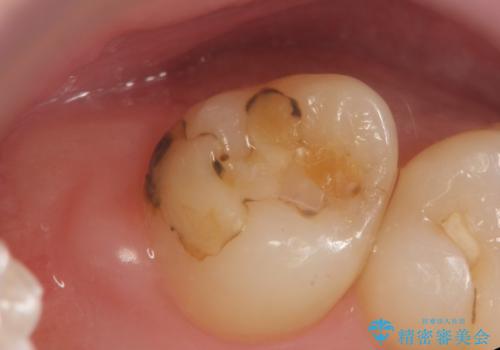

夜間の歯ぎしりによるチッピング、破折をふせぐため、ナイトガード使用をお勧めしています。

- かみ合わせや歯ぎしりが強すぎる方はセラミックが割れてしまう可能性があります